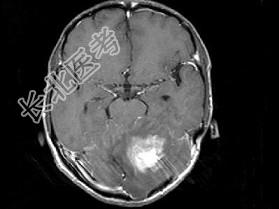

- 单项选择题男,41岁, 左枕部疼痛,右侧肢体乏力, 并渐进性加重半个月,右侧肢体乏力, 行走不稳,根据所提供图像, 最可能的诊断是 ( )

A、(小脑)血管母细胞瘤

B、(小脑)髓母细胞瘤

C、(小脑)炎性肉芽肿

D、(小脑)转移瘤

E、(小脑)星形胶质细胞瘤Ⅰ~Ⅱ级